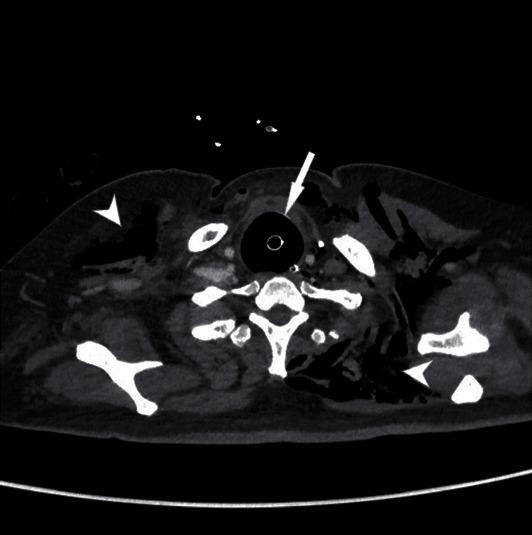

COVID-19 associated severe respiratory failure frequently requires admission to an intensive care unit, tracheal intubation, and mechanical ventilation. Among the risks of prolonged mechanical ventilation under these conditions, there is the development of tracheoesophageal fistula. We describe a case of a severe COVID-19 associated respiratory failure, who developed a tracheoesophageal fistula. We hypothesized that one of the mechanisms for tracheoesophageal fistula, along with other local and general risk factors, is the local infection due to the location of the virus itself in the tracheobronchial tree. The patient was managed successfully with surgical intervention. This case highlights the increased risk of this potentially life-threatening complication among the COVID-19 patient cohort and suggests a management strategy.

https://cdn.ncbi.nlm.nih.gov/pmc/blobs/2c85/8014238/94372e58ede1/CRIS2021-6645518.003.jpg

https://cdn.ncbi.nlm.nih.gov/pmc/blobs/2c85/8014238/4d346df252ca/CRIS2021-6645518.001.jpg

https://cdn.ncbi.nlm.nih.gov/pmc/blobs/2c85/8014238/9118d9ac8c0e/CRIS2021-6645518.002.jpg